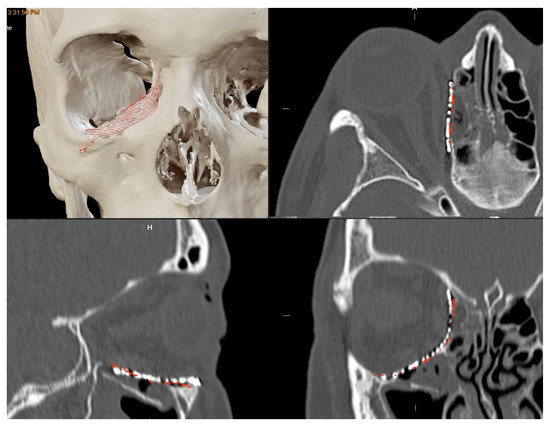

Initially, mirroring techniques were employed to achieve a virtually ideal reconstruction of the orbital defect. Subsequently, the STL file of the plate was uploaded into the Brainlab Element Software 4.0. The 3D-POTM’s STL files were digitally overlaid onto the simulated optimal 3D virtual orbital reconstruction. The software’s tools were then used to manipulate the plate object, adjusting its position within the reconstructed orbit created via mirroring. To ensure a precise fit to the boundaries of the mirroring, the “object management” tool was employed to cut the plate. This process allowed for the customization of the plate’s shape, ensuring optimal adaptation to the specific orbital defect and the mirrored orbit. In this stage, digital planning was employed to determine the required trimming of surplus mesh components, and the ideal placement for the implant was computed by two senior surgeons. This assessment drew upon the data from the STL file and preoperative scans analyzed through Brainlab Elements Contouring, version 4.0 (Brainlab, Feldkirchen, Germany). In contrast, a bending plate was not designed. The preformed meshes utilized in the study (3D Orbital Floor Plate, Stryker Corp., Kalamazoo, MI, USA) were already shaped appropriately to accurately reproduce the orbital floor and/or the transition zone between the orbital floor and medial orbital wall, without requiring bending. The estimation and verification of the implant’s location within the orbit, as well as its connections with the anatomical structures of the orbit, were subsequently confirmed (Figure 1). In all cases, presurgical VSP took place before the patient’s hospitalization, primarily in the outpatient clinic. The process of virtual planning, including the manipulation of 3D models and the determination of surgical approaches, was conducted before the hospitalization. The navigation system (Brainlab Curve, Brainlab, Munich, Germany) was loaded with both the preoperative CT scan and the STL file of the 3D-preformed implant.

Figure 1. Preoperative Virtual Planning. The 3D-preformed titanium mesh’s STL files were virtually overlaid to align with the “ideal orbital reconstruction” achieved by using the mirrored unaffected contralateral side as a reference. In red: STL files for 3D-preformed titanium mesh. Light blue: mirrored orbit. Green: safe orbit.